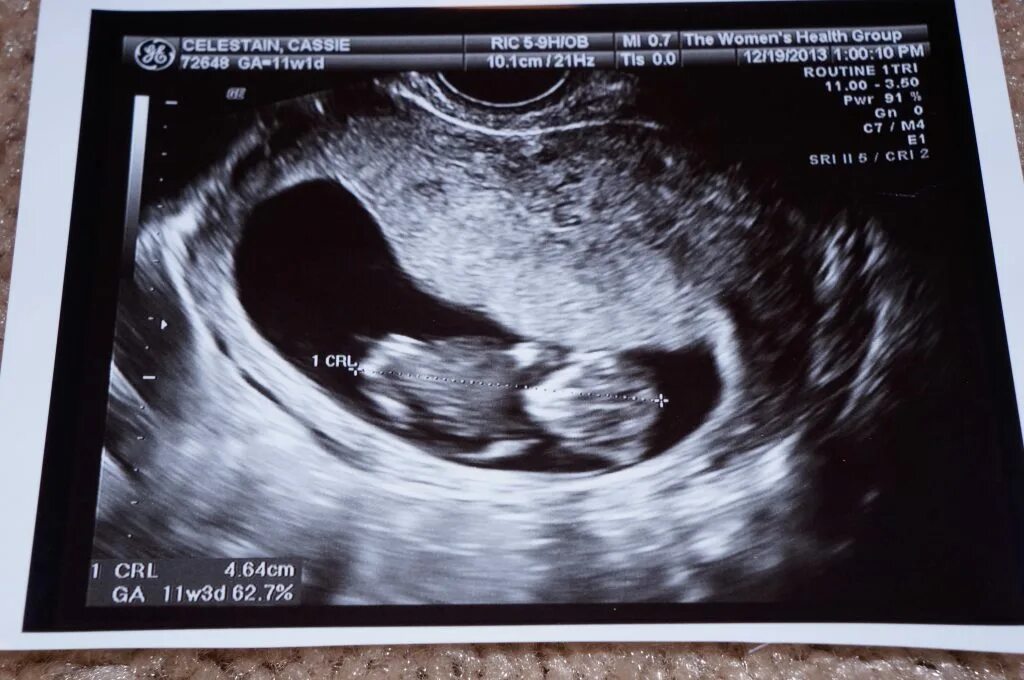

11 недель ощущения